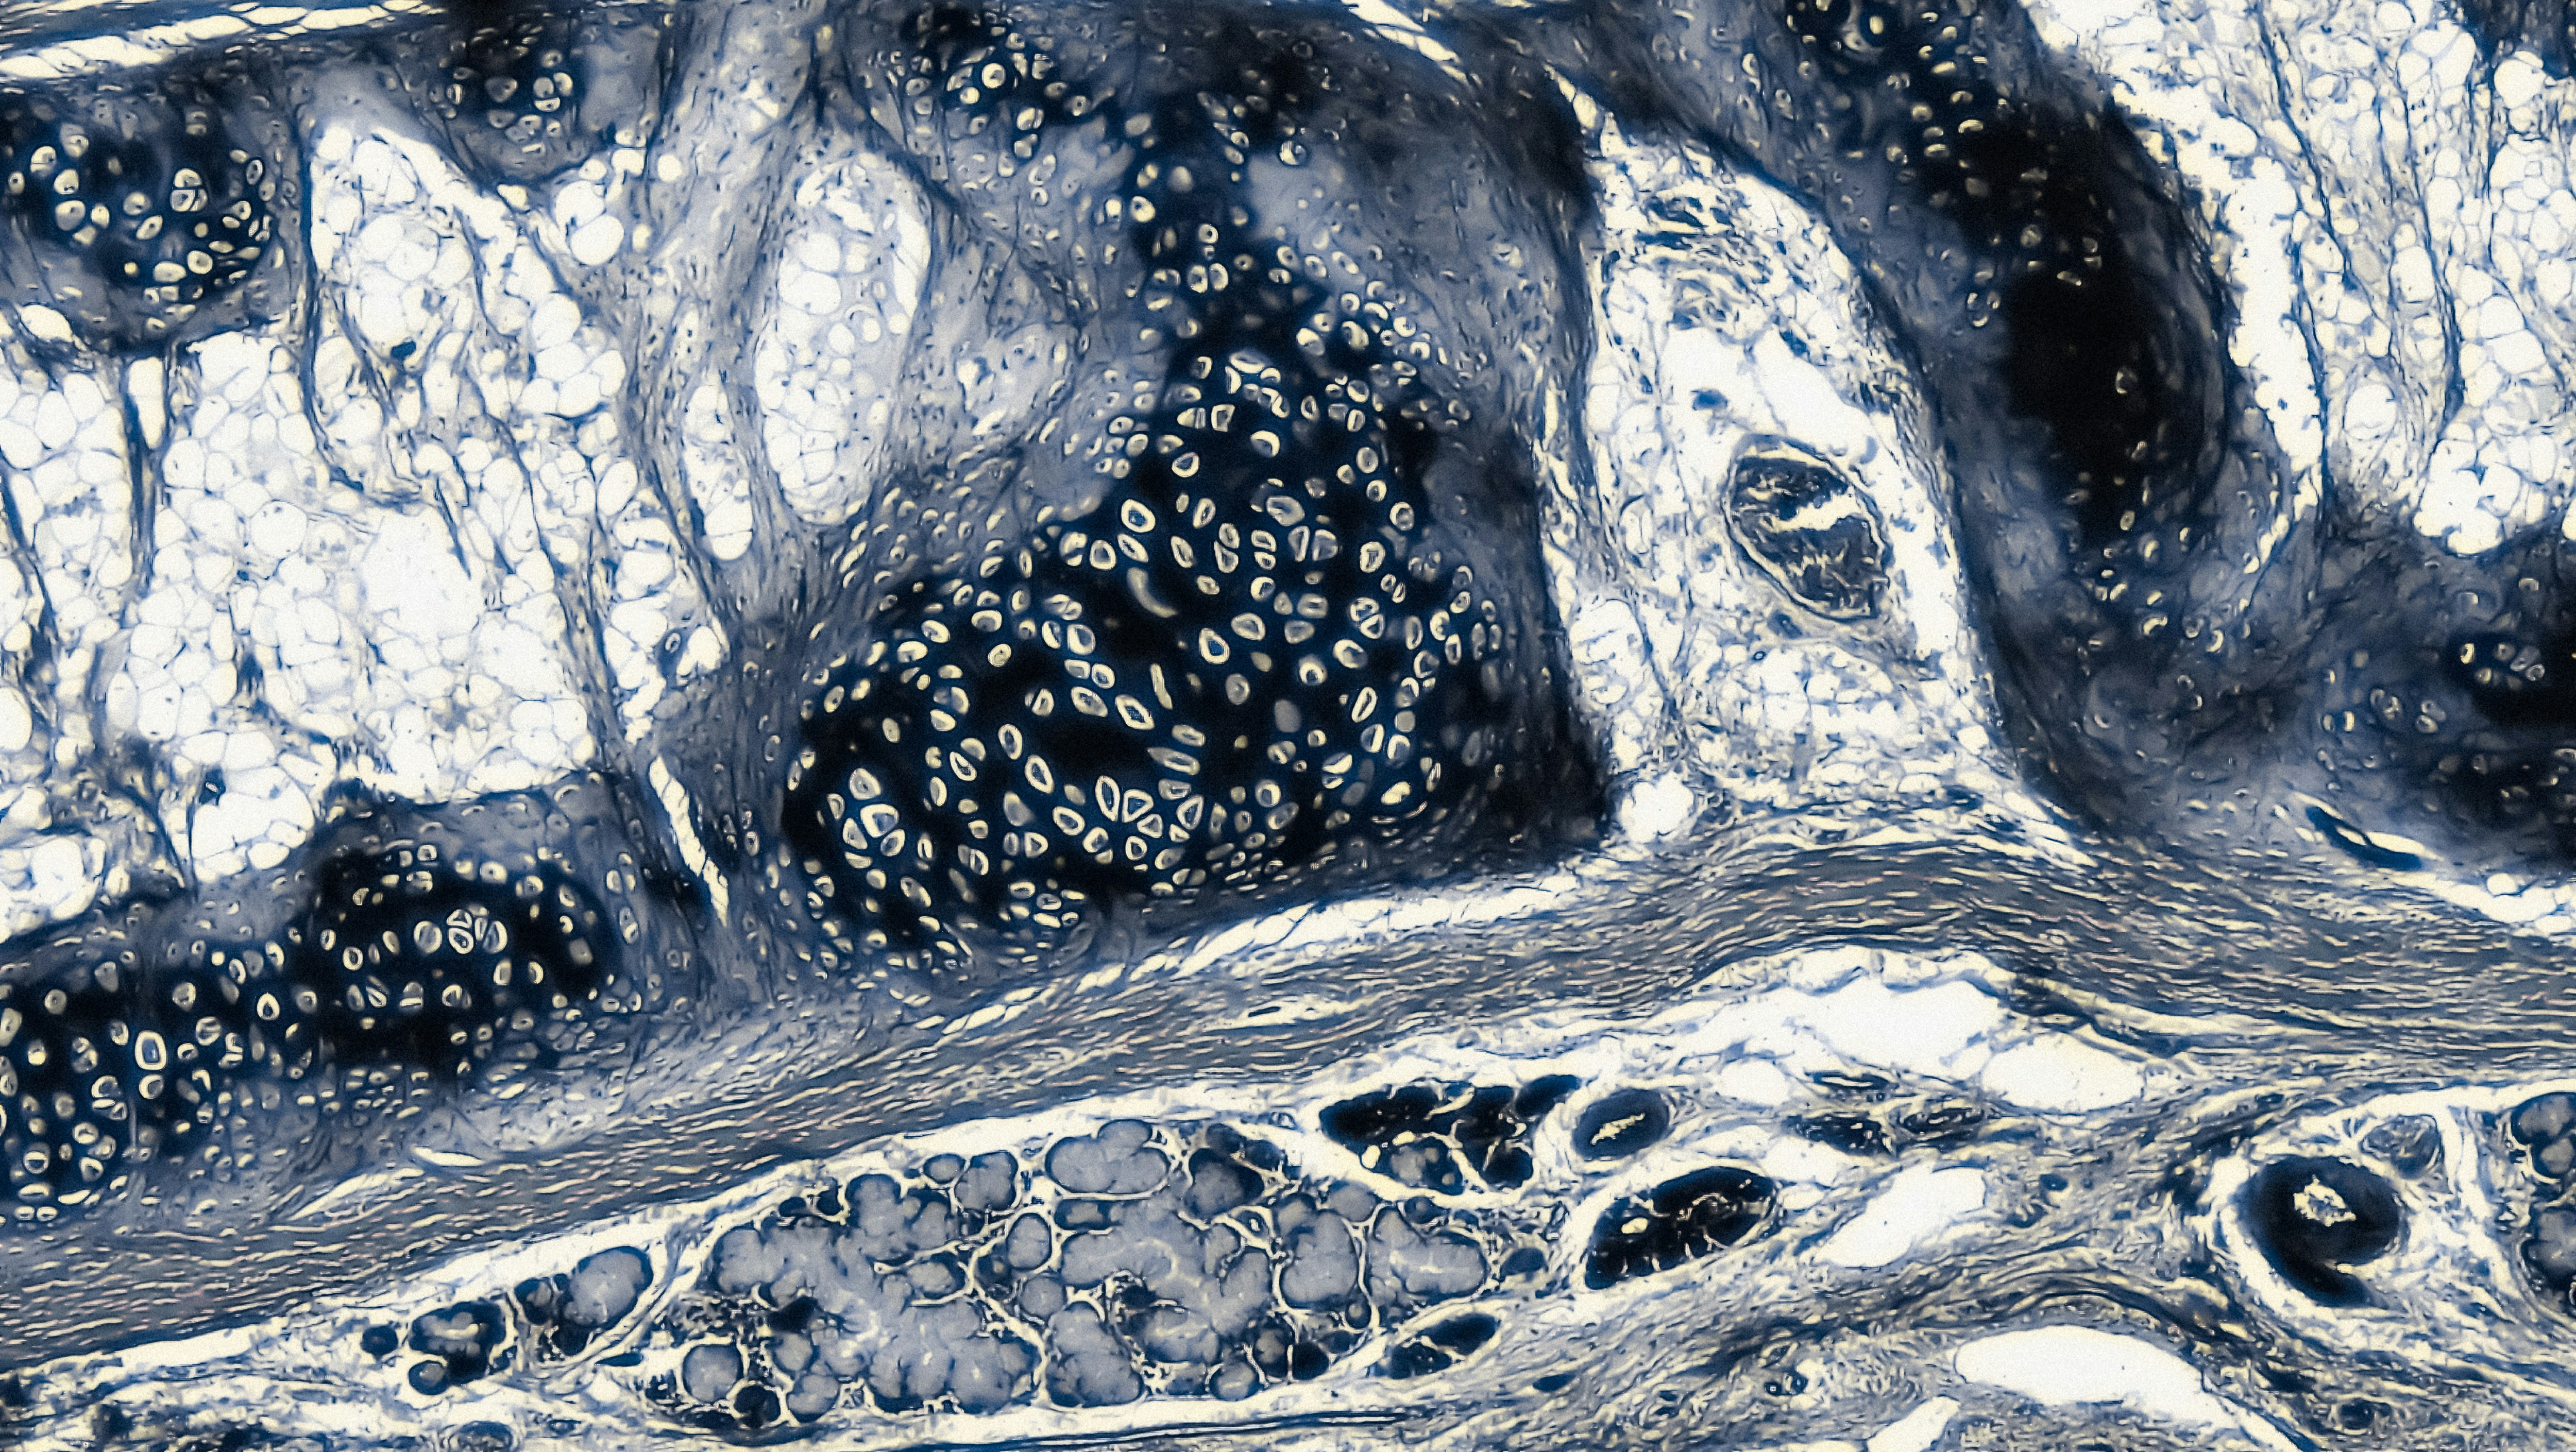

Connective Tissue: Elastic Cartilage cross section: mammalian elastic cartilage magnification: 40x https://www.flickr.com/photos/146824358@N03/41855667361/